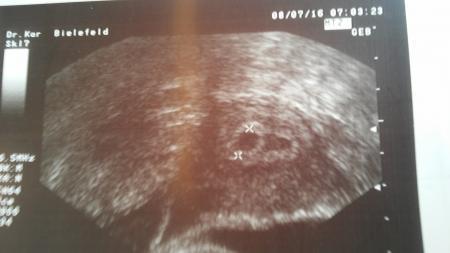

Ich war heute beim Arzt,leider die Vertretung die während des Ultraschalls gar nicht mit mit sprach und mir danach nur das Bild in den Mutterpass legte... Sind hier erfahrene Mamis die das sehen können?

Da ist nur eine Fruchthöhle markiert. Dann wird da auch nur eines sein.

Die Ärztin geht anscheinend von nur einer Fruchthöhle aus. Allerdings ist da daneben schon auch noch was. Aber eventuell auch nur etwas Flüssigkeit oder so. LG

Ja das sagen nämlich alle. Eine Freundin ist medizinische Fachangestellte und meinte es könnten 2 sein oder eben nur ein Hämatom. Also heißt es bis zum nächsten Warten

Meine Zwillinge sahen anfangs auch so aus. Allerdings wurde erst in der 7 ssw. Die Zwillinfsschwangerschaft bestätigt. Vorher hieß es das es entweder ein Zwilling oder ein Hämatom ist. Leider hat sich eins nach der 9 ssw nicht mehr weiter entwickelt

Hallo mein erstes us bild vom kleinen sah genauso aus dachte bzw hoffte dann auch auf zwei. Allerdings war beim nächsten mal nur eine fruchthulle zu sehen. Daher hilft grübeln nicht. Lg nita